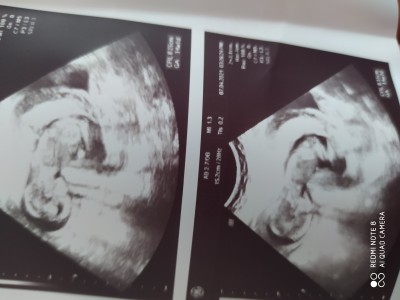

Arkadaşlar 14+2,3 günlük gebelik bugün hastaneden geldim doktor cinsiyet tahmini yaptı ama arkası dönük net bir şey göremiyorum boşluk kıza benziyor gibi dedi ama daha erken dedi organları net tmamalanmıyo daha bu haftada dedi sizce neye benziyor siz doktorun dediğinden ne çıkardınız zaten bir baktı arkası dönük bacakları kapalı

dedi 2,3 haftaya netleşwbilşr dedi